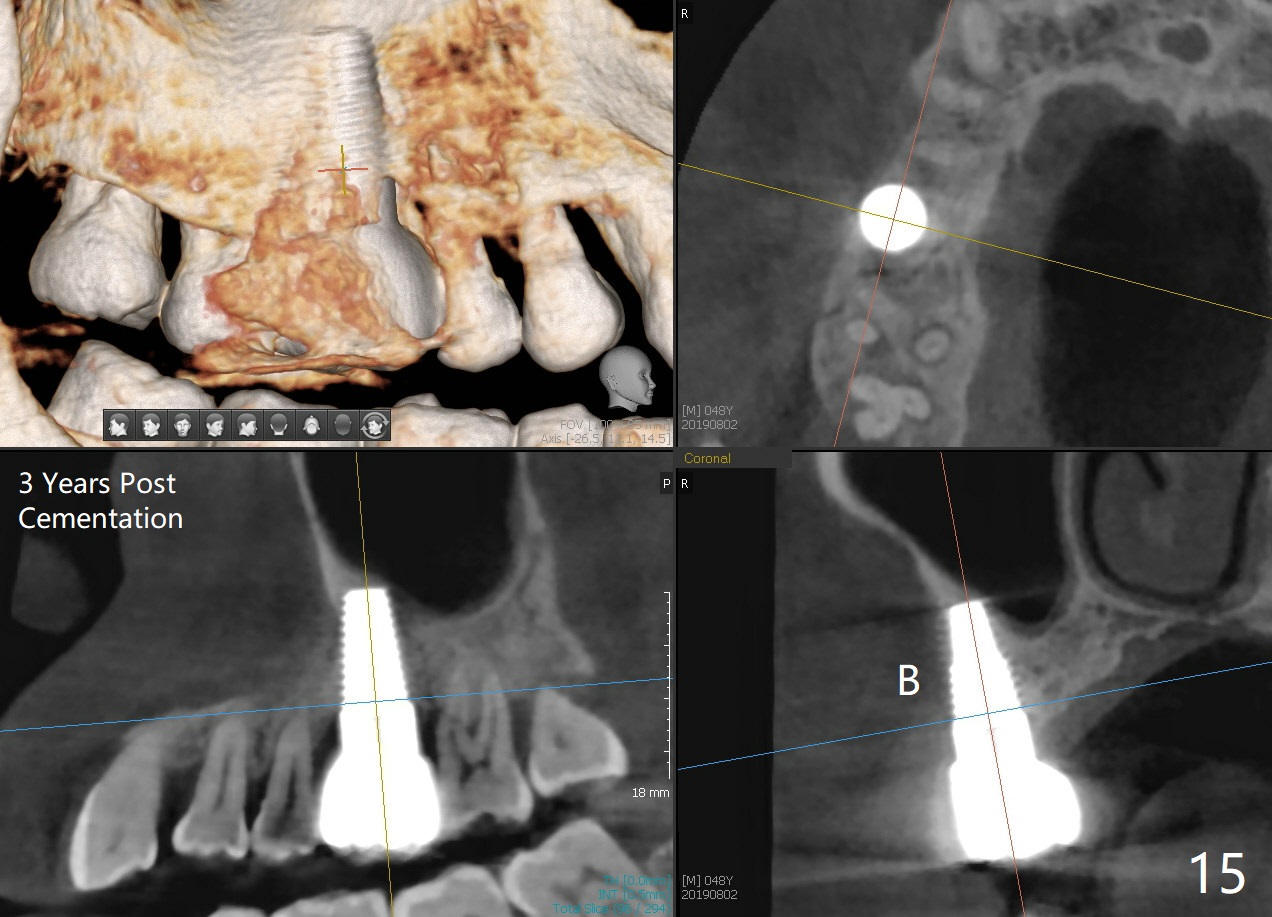

The patient returns for restoration 23 months postop; the implant appears to have been osteointegrated (Fig.14). There is no buccal or palatal gingival recession. The large implant appears to close the large defect readily and enhances bone/implant contact. The buccal plate seems to be thin 3 years post cementation, although there is no sign of periimplantitis (Fig.15). The mesial papilla is severely recessive with open contact 3 years 5 months post cementation. BW shows DO caries of the teeth #2, 4 and 30. The crown is removed for better oral hygiene by fabricating a provisional and conservative composite for #4. Water Pik is recommended.